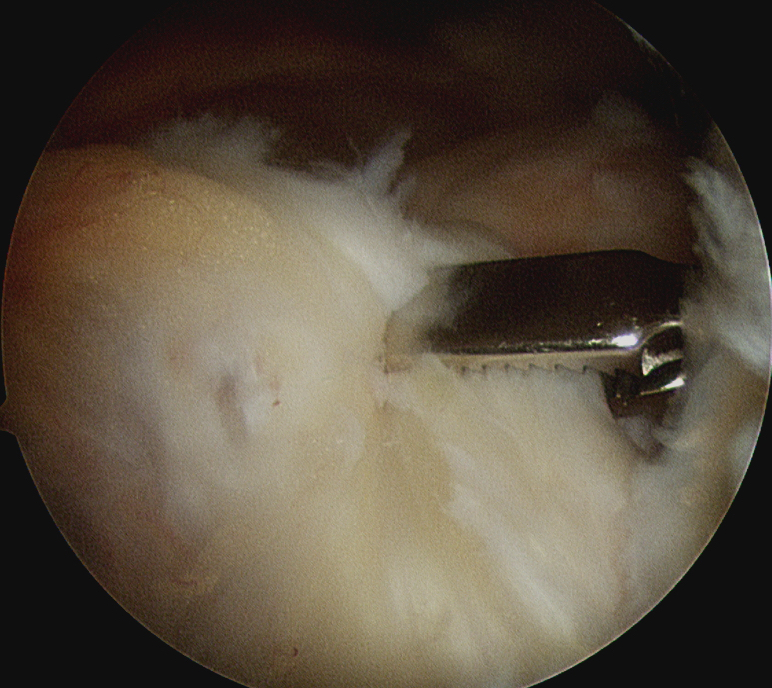

Repair infraspinatus with a combination of margin convergence and posterior suture anchors onto posterior greater tuberosity

- suture anchors repair to greater tuberosity +/- subscapularis

Repair with suture anchors to greater tuberosity and to subscapularis